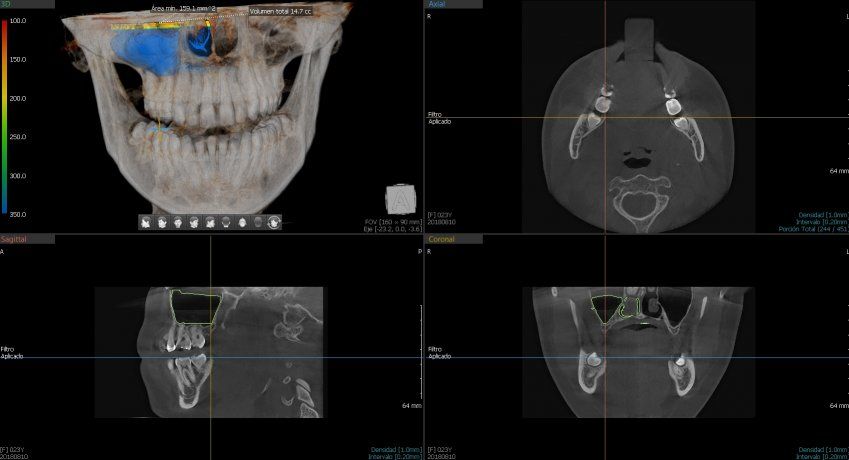

Green 16/18 ofrece una gama de campos de visión seleccionables. Multi FOV permite al usuario seleccionar el modo FOV óptimo y minimizar la exposición a áreas que no son la región de interés. Seleccione el tamaño adecuado de FOV entre 16×9/18×10, 12×9/13×10, 8×9 y 5×5 basado en una particular necesidad de diagnóstico. Cubre la región del arco completo, seno y la ATM izquierda / derecha y es adecuado para la mayoría de los casos de cirugía oral así como la cirugía de implantes múltiples. También puede medir el volumen de la vía aérea.